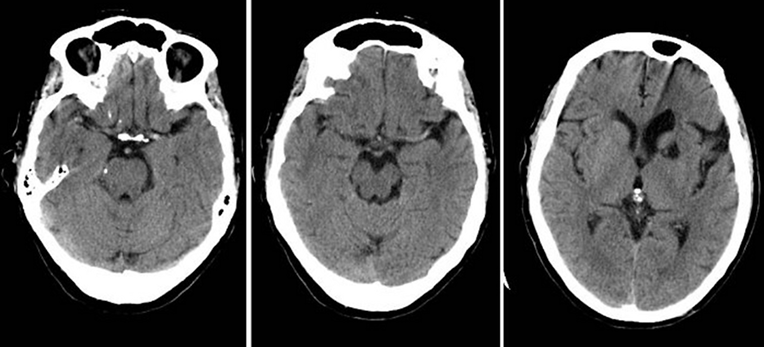

Explainable AI changes this. It shows the logic behind each detection, making it easier for specialists to verify findings. This transparency is especially important for identifying hypodense lesions, which often require careful evaluation due to their subtle appearances across CT & MRI scans in various anatomical regions due to their subtle contrast differences.

Hypodense lesions can be difficult to identify because they share almost visual similarities with the surrounding tissue. Even experienced radiologists may spend significant time reviewing multiple slices of a scan.

AI imaging applications assist in speeding up this process—but only if the accurate data behind them is correct. The strength of any AI model depends on the quality of its training data. When the segmentation is flawed or inconsistent, the model’s output becomes unreliable. This is why high-quality AI segmentation is essential. It ensures every pixel and boundary is segmented with precision. Hypodense lesions can indicate different pathologies depending on the organ, ranging from cerebral infarcts to hepatic cysts, splenic lesions, renal abnormalities, or soft-tissue changes. AI models must be trained on diverse, explainable datasets that reflect this anatomical variability.

We segmented hypodense lesions with pixel-level accuracy, ensuring every boundary and shape is captured correctly, whether the lesion is in the brain, abdomen, or soft tissues.